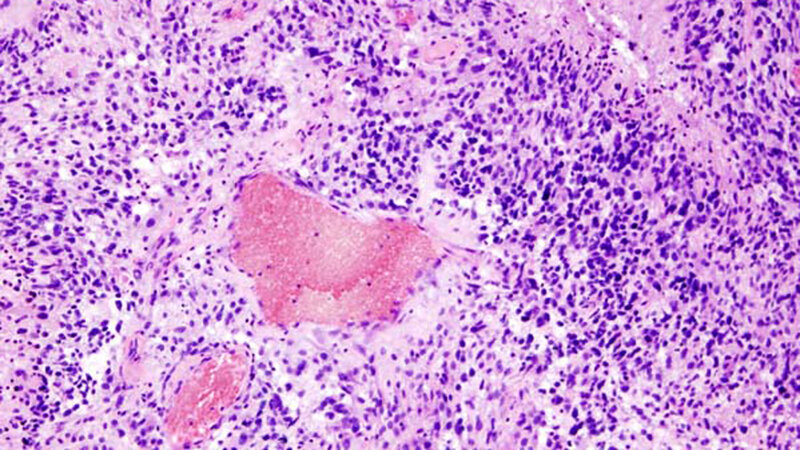

Das Glioblastom, ein seltener, aber äußerst bösartiger Hirntumor, kann nach der Operation durch die Kombination aus Chemotherapie und Radiotherapie zurückgedrängt werden. Eine aktuelle Studie zeigt, dass auch hochbetagte Patienten davon profitieren. Bislang erhielten sie – gestützt auf einen Gentest – entweder eine Chemo- oder eine Strahlentherapie. Eine gleichzeitige Radiotherapie kombiniert mit Temozolomid hat die Überlebenszeit dieser Patientengruppe verlängert.

Die meisten Menschen mit einem Glioblastom sind über 65 Jahre alt, wenn ihr Hirntumor entdeckt wird. Eine Operation kann den Tumor in der Regel nicht heilen. Strahlen- und Chemotherapie können jedoch die Lebenszeit verlängern und bei den meisten Patienten auch die Lebensqualität verbessern. Die Behandlung ist jedoch anspruchsvoll und die Nebenwirkungen von Strahlen- und Chemotherapie können sich verstärken. „Wir waren deshalb bisher sehr zurückhaltend, die Strahlentherapie in Kombination mit Chemotherapie älteren Patienten anzubieten, zumal diese häufig Begleiterkrankungen haben, die die Verträglichkeit der Behandlung verschlechtern können“, berichtet Prof. Dr. med. Stephanie Combs, Direktorin der Klinik und Poliklinik für Radioonkologie und Strahlentherapie an der Technischen Universität München.